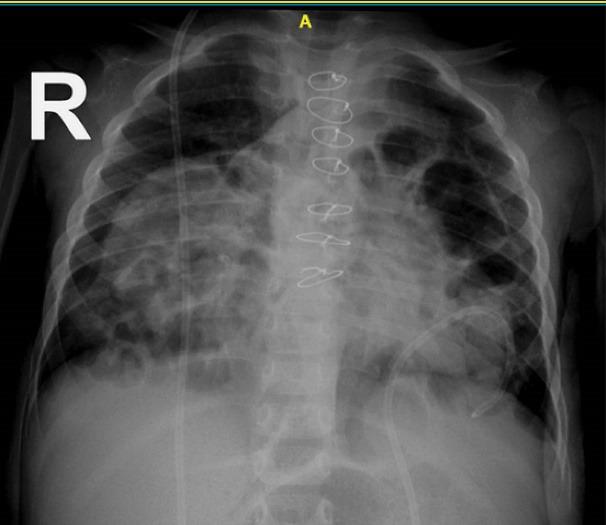

A male infant with a history of ventriculoperitoneal (VP) implantation due to congenital hydrocephalus presented with fever and lethargy at the age of 8 month-old. Pericardial effusion was detected in transthoracic echocardiography, and he underwent pericardial window operation and was discharged in a stable condition. At 11 months of age, he presented again with fever, lethargy, recurrent vomiting, and respiratory distress. In both plain chest radiography and transthoracic echocardiography, VP shunt migration to the heart cavity was observed. The VP shunt had entered into the right ventricle after perforating the diaphragm and pericardium. The patient underwent open-heart surgery due to vegetation at the tip of the VP shunt inside the right heart. Vegetation was removed and the tip of the shunt was returned to the peritoneal cavity. Two weeks after discharge, the patient presented again with symptoms of tachypnea and lethargy. The imaging revealed the entry of the VP shunt about two centimeters into the anterior mediastinum. The patient was transferred to the operation room and the VP shunt was shortened and re-inserted into the peritoneal cavity. Antibiotic treatment was continued for six weeks and the patient was discharged in stable condition. In follow-up visits after two years, the VP shunt functioned well and no particular complication was observed. This case demonstrates that in patients with VP shunt implantation presenting with pulmonary and cardiac symptoms such as respiratory distress, pericardial effusion, and cardiac tamponade after VP shunt implantation, the possibility of VP shunt catheter migration to the mediastinal cavity should be considered.

一名因先天性脑积水接受脑室腹腔(VP)分流术的男婴,8个月大时出现发热和嗜睡症状。经胸超声心动图检查发现心包积液,随后他接受了心包开窗手术,出院时病情稳定。11个月大时,他再次出现发热、嗜睡、反复呕吐和呼吸窘迫症状。胸部X线平片和经胸超声心动图检查均观察到VP分流管移入心脏腔室。VP分流管在穿透膈肌和心包后进入右心室。由于右心室内VP分流管尖端出现赘生物,该患者接受了心脏直视手术。赘生物被清除,分流管尖端被放回腹腔。出院两周后,患者再次出现呼吸急促和嗜睡症状。影像学检查显示VP分流管进入前纵隔约两厘米。患者被转至手术室,VP分流管被缩短并重新插入腹腔。抗生素治疗持续六周,患者出院时病情稳定。在两年后的随访中,VP分流管功能良好,未观察到特殊并发症。该病例表明,对于接受VP分流术的患者,若术后出现呼吸窘迫、心包积液和心脏压塞等肺部和心脏症状,应考虑VP分流管导管移入纵隔腔的可能性。